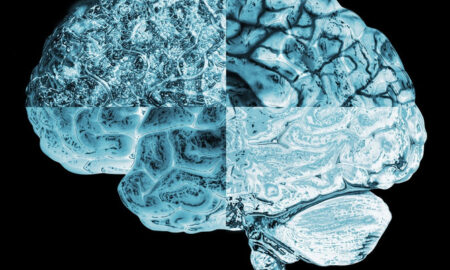

29.3KNaukaNaučnici otkrili da se ženama tokom menstruacije mijenja cijeli mozak

Navale hormona koje stoje iza menstrualnog ciklusa ne utječu samo na reproduktivnu anatomiju - one također preoblikuju mozak.

21.8KZdravljeNaučnici otkrili da se ženama tokom menstruacije mijenja cijeli mozak

Navale hormona koje stoje iza menstrualnog ciklusa ne utječu samo na reproduktivnu anatomiju - one također preoblikuju mozak.

25.8KZdravljeNaučnici otkrili da se ženama tokom menstruacije mijenja cijeli mozak: EVO KAKO

NAVALE hormona koje stoje iza menstrualnog ciklusa ne utječu samo na reproduktivnu anatomiju - one također preoblikuju mozak.